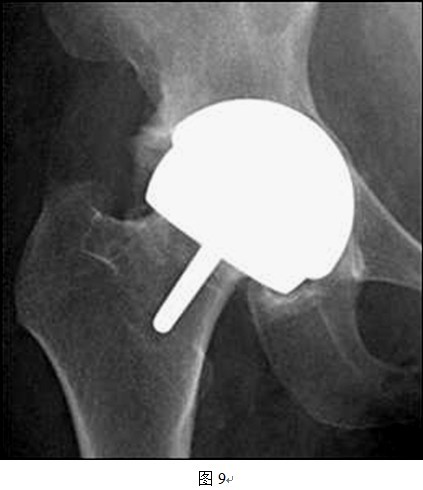

(1)头和臼假体之间有时很难良好匹配

DDH患者的髋臼发育不规律,头臼的匹配程度远远差于正常髋关节,而THRA的头臼假体间是一对一大小匹配,所以对于发育偏小的髋臼,按照髋臼侧决定THRA假体套件大小会出现股骨头过度磨锉,造成切迹;而按照股骨侧决定假体套件大小则会造成髋臼过度磨锉,大量骨质丢失,影响稳定性(图7、8所示即为以股骨侧决定假体大小时,髋臼侧出现过度磨锉,以致锉穿髋臼底部)。同样道理,对于发育偏大的髋臼,按照髋臼侧选择假体大小会造成人为的股骨颈缩窄(图9中所示病例以髋臼侧决定假体大小,导致股骨侧假体过大,反衬出股骨颈细小),而按照股骨侧决定假体型号则可能会出现髋臼软骨磨锉不充分,也可能影响髋臼假体稳定性(图10中所示病例以股骨侧选择假体大小,原始髋臼对于臼杯假体相对偏大,臼杯边缘的软骨尚未充分磨锉)。

图中所示,按照髋臼侧决定假体大小原则,匹配的股骨侧假体较股骨头颈来说偏大,造成人为股骨颈缩窄现象。